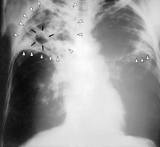

Sus primeras investigaciones no dieron los resultados esperados debido a la mala calidad de las imágenes fluoroscópicas. Pero las técnicas se fueron perfeccionando, y en 1935 pudo desarrollar, en el hospital alemán de Río, un método rápido y barato para realizar pequeñas radiografías pulmonares en una película fotográfica de 50 ó 100 mm. Este sistema, llamado abreugrafía en Brasil y más tarde fotoradioscopia en España, se usó durante décadas, con excelentes resultados, para la detección precoz de la tuberculosis. Gracias a la fotoradioscopia, se redujo la mortalidad provocada por esa enfermedad. Tal fue su éxito, que en 1957 se creó en Brasil la Sociedad Brasileña de Abreugrafía.

Con el desarrollo de los antibióticos y el mayor reconocimiento de la peligrosidad de la exposición a los rayos X, la fotoradioscopia obligatoria de la población se abandonó en muchos países en la década de 1970, y la Organización Mundial de la Salud recomendó su eliminación total en 1999. Hoy en día sólo se usa en algunos países y en grupos de población específicos, como reclusos, ancianos e inmigrantes procedentes de países con alta incidencia de tuberculosis.